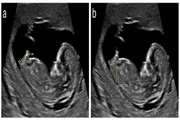

A consultation meeting was held on October 31 at the Radiology Research Center of Tehran University of Medical Sciences, bringing together faculty members, senior managers, and researchers to discuss collaborative opportunities. Dr. Ghanati, head of the center, and Dr. Firouznia, deputy research director, highlighted strategies for enhancing international scientific partnerships. Dr. Torabi, vice president of international affairs, emphasized the importance of increasing the scientific influence of faculty members globally. The session included discussions to address academic challenges and aimed to strengthen research synergies, with plans for similar future meetings